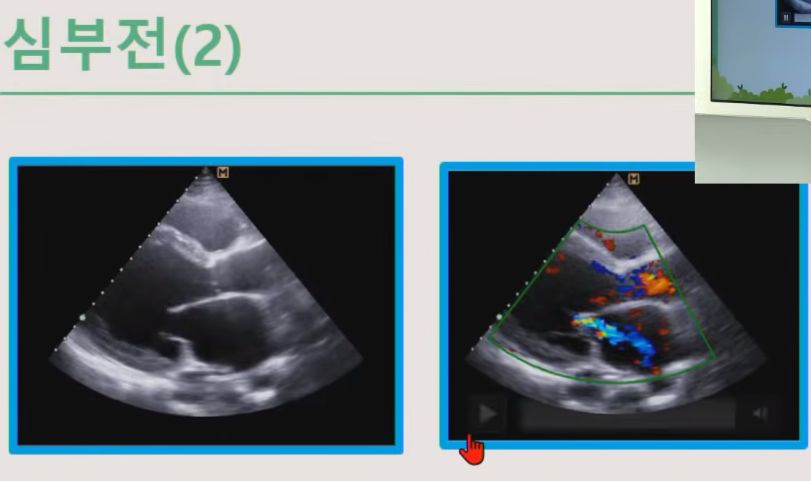

심부전

심장이 잘 못 뛰면 판막이 잘 안 닫혀서 역류가 일어난다.